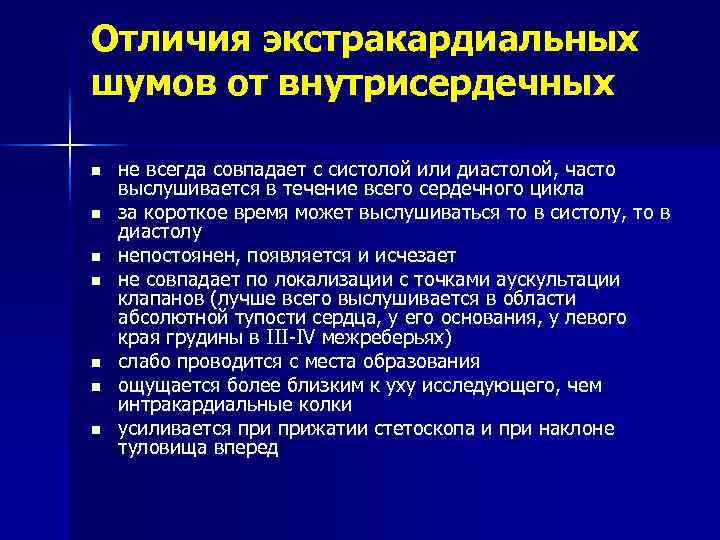

Отличия экстракардиальных шумов от внутрисердечных n n n n не всегда совпадает с систолой или диастолой, часто выслушивается в течение всего сердечного цикла за короткое время может выслушиваться то в систолу, то в диастолу непостоянен, появляется и исчезает не совпадает по локализации с точками аускультации клапанов (лучше всего выслушивается в области абсолютной тупости сердца, у его основания, у левого края грудины в III-IV межреберьях) слабо проводится с места образования ощущается более близким к уху исследующего, чем интракардиальные колки усиливается прижатии стетоскопа и при наклоне туловища вперед